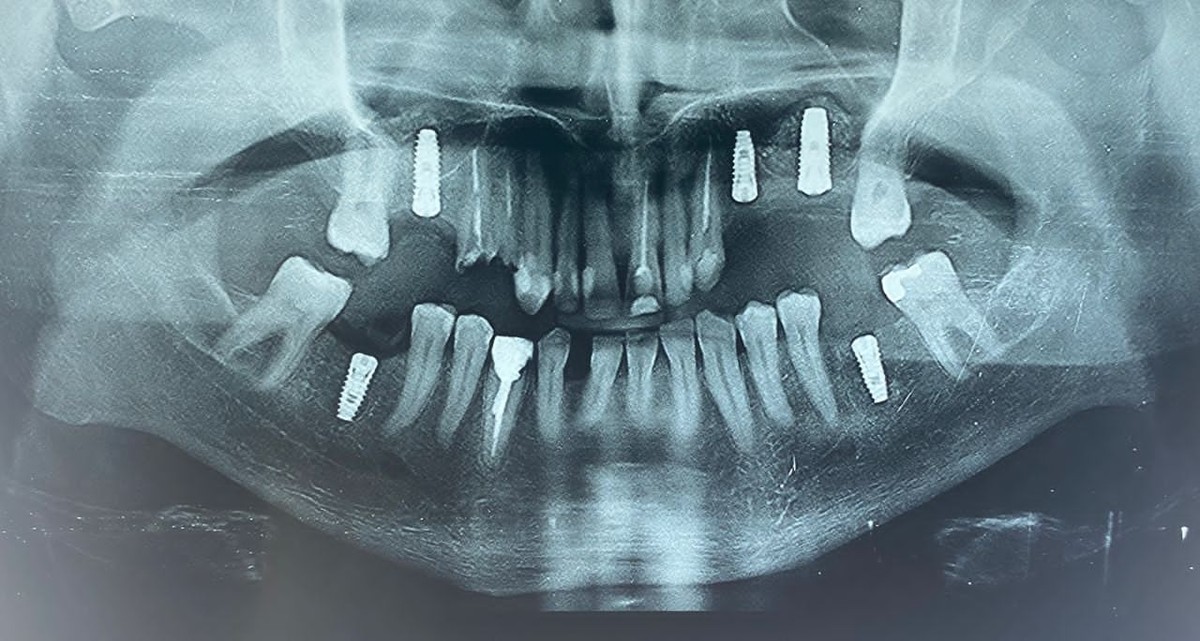

لمینیت سرامیکی دندان(طراحی لبخند) کامپوزیت ونیر دندان (طراحی لبخند) ایمپلنت و کلیه جراحی های تخصصی فک و صورت توسط جراح و متخصص دهان و فک و صورت کلیه خدمات دندانپزشکی به صورت تخصصی با بالاترین کیفیت توسط بهترین دندانپزشکان و در محیط کاملا vip

کلینیک دندانپزشکی دندانپزشکی زیبایی مرکز کامپوزیت دندان مرکز لمینت دندان مرکز ارتودنسی دندان دندانپزشکی کودکان دکتر ارتودنسی کودکان دندانپزشکی اطفال دکتر دندانپزشک متخصص ایمپلنت دندانپزشکی شبانه روزی عصب کشی جراح دندانپزشک جراح دندان عقل جراح لثه جراحی لثه با لیزر متخصص درمان ریشه دندان متخصص لمینت دندان متخصص ارتودنسی ایمپلنت فوری اصلاح طرح لبخند بلیچینگ دندان دندانپزشکی بدون درد کاشت دندان متخصص پروتز دندان ایمپلنت دیجیتال لیفت لثه با لیزر دندانپزشکی با لیزر دکتر دندانساز ایمپلنت اقساطی مشاهده بیشتر